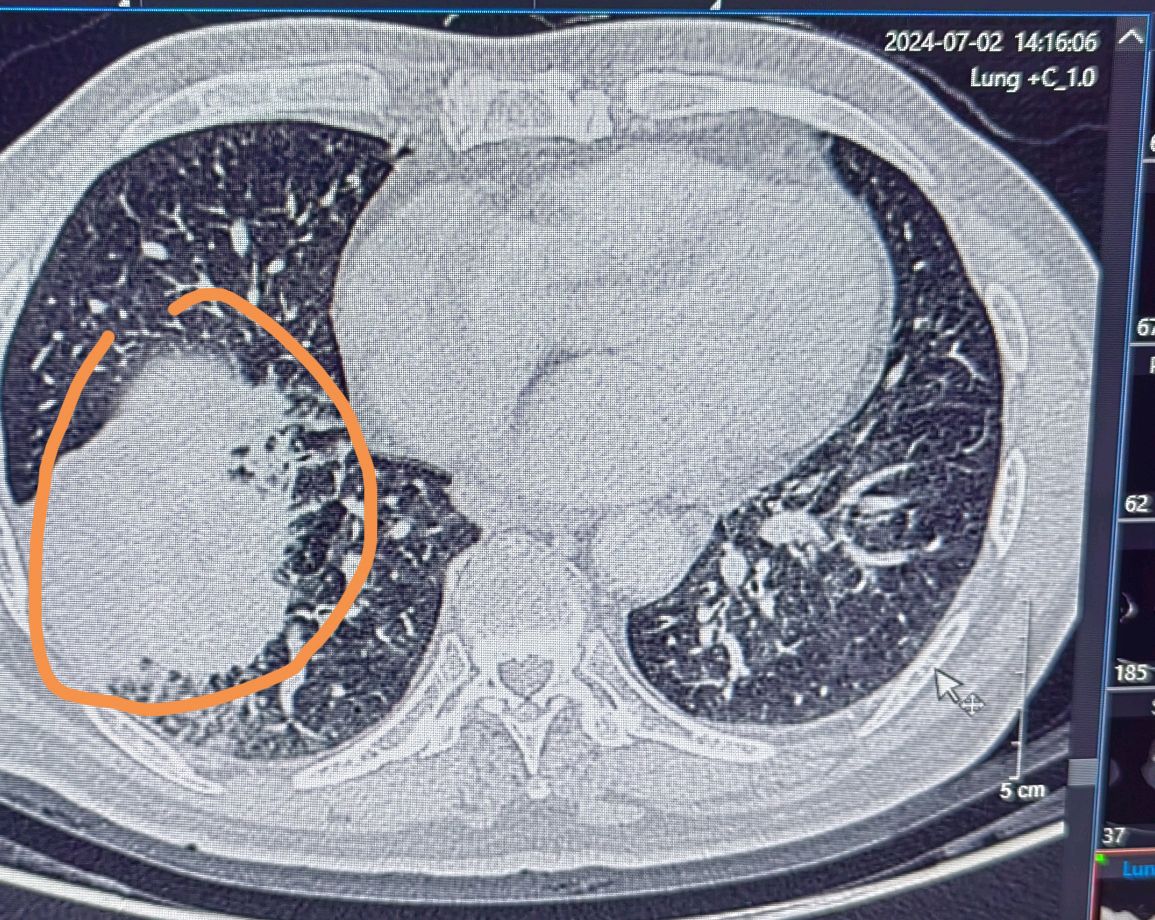

局部晚期肺癌经过化疗联合免疫治疗后一年手术

局部晚期非小细胞肺癌伴上腔静脉侵犯的外科治疗--两切口入路手术

新辅助治疗后手术切除——中晚期肺癌患者的机遇